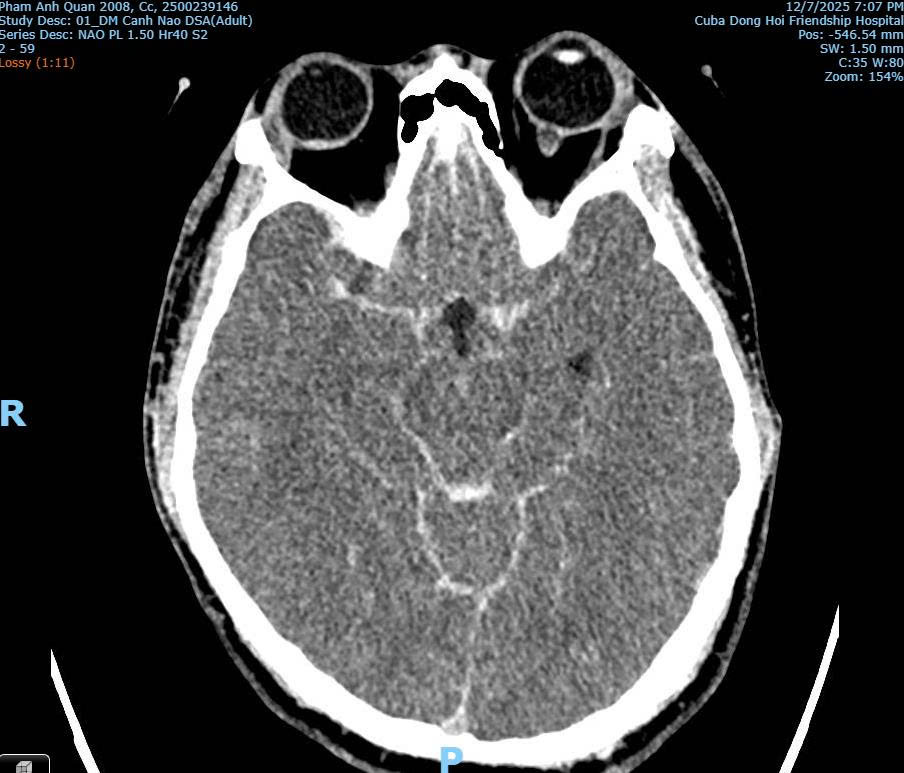

Hình ảnh CT/MRI: Xuất huyết dưới nhện do vỡ phình mạch máu não của bệnh nhân Phạm Anh Q. thời điểm tại Bệnh viện Hữu nghị Việt Nam – Cuba Đồng Hới

Phân tích từ hình ảnh chẩn đoán, bác sĩ Hùng cho biết không phát hiện tổn thương xương cột sống cổ, không có tổn thương vòm sọ, không có tổn thương não do lực tác động bên ngoài. Đồng thời chỉ ghi nhận xuất huyết não lan tỏa và phù não, điển hình của vỡ phình mạch não.

Bác sĩ Hùng khẳng định theo hình ảnh chuyên môn y khoa từ chẩn đoán thì không có dấu hiệu nào cho thấy nạn nhân bị đánh với lực đủ mạnh để gây gãy cổ hoặc chấn thương sọ não do tác động ngoại lực.